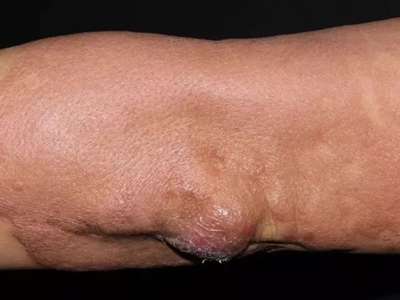

胳膊

小疙瘩

瘤型麻风胳膊长表面光滑的小疙瘩图

瘤型麻风患者的胳膊可出现淡粉色的隆起性光滑斑疹,类似于小疙瘩,有弥漫性浸润,表面光亮,边界较为模糊,有扩散趋势,部分患者皮损处存在不适感,或者酥酥麻麻的感觉异常。